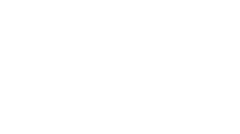

نحوه انجام بلوک عصبی

انجام بلوک عصبی معمولاً تحت هدایت دستگاه فلوروسکوپی (رادیوگرافی زنده) یا سونوگرافی است. ابتدا ناحیه مورد نظر ضدعفونی شده و سپس سوزن به دقت در نزدیکی عصب یا فضای اپیدورال وارد میشود. پس از اطمینان از محل صحیح، دارو تزریق میگردد. کل فرآیند معمولاً کمتر از ۳۰ دقیقه طول میکشد و نیاز به بیهوشی عمومی ندارد.